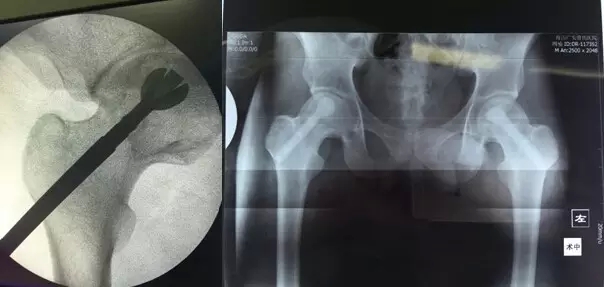

3月29日,舟山廣安醫(yī)院危立軍副院長為一名29歲的雙側(cè)股骨頭早期壞死患者成功實施了股骨頭壞死減壓、病灶清除、可注射人工骨植入術(shù)。這是當(dāng)前國際上在治療此類疾病的最先進(jìn)的微創(chuàng)手術(shù)技術(shù)。該項技術(shù)可以有效阻止股骨進(jìn)一步頭壞死而導(dǎo)致關(guān)節(jié)軟骨面塌陷,通過再造創(chuàng)面誘導(dǎo)骨再生、成骨而達(dá)到治愈目的。

治療股骨頭壞死的關(guān)鍵是終止病變進(jìn)展,在股骨頭壞死的早期階段,保留患者自身髖關(guān)節(jié)具有很高的臨床和社會價值。使之有可能往良性的軌道上發(fā)展。廣安醫(yī)院開展的“股骨頭壞死減壓、病灶清除、可注射人工骨植入術(shù)”,在保護(hù)已發(fā)生的壞死骨基礎(chǔ)上,同時通過生物學(xué)反應(yīng)促進(jìn)骨再生和病變組織修復(fù),有效恢復(fù)承重能力,防止股骨頭變形塌陷。該技術(shù)手術(shù)切口長約1-2厘米,創(chuàng)傷小,費(fèi)用低,恢復(fù)快,術(shù)后第二天即可出院,門診治療。